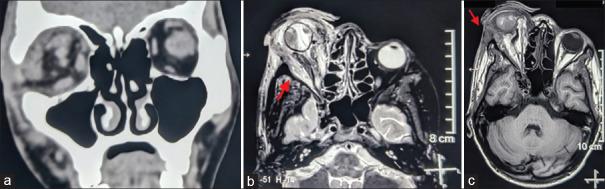

Carotid-cavernous fistula (CCF) is a rare condition involving an abnormal communication between the carotid artery and the cavernous sinus. We present a unique case of posttraumatic unilateral CCF initially misdiagnosed as a corneal melt with iris prolapse and orbital cellulitis. The patient, a 25-year-old male, experienced swelling, bleeding, and sudden vision loss in the affected eye following a fall. Imaging confirmed a direct CCF, and the patient underwent endovascular coiling, evisceration, and prosthetic replacement. Partial loss of levator palpebrae superioris muscle function was observed postprocedure. This case underscores the diagnostic challenge of CCF and highlights the significance of early and accurate diagnosis for appropriate management.

颈动脉海绵窦瘘(CCF)是一种罕见的病症,涉及颈动脉与海绵窦之间的异常连通。我们报告了一例独特的创伤后单侧CCF病例,最初被误诊为角膜溶解伴虹膜脱垂和眼眶蜂窝织炎。该患者为一名25岁男性,跌倒后患眼出现肿胀、出血和突然失明。影像学检查证实为直接CCF,患者接受了血管内栓塞、眼球摘除和假体置换。术后观察到上睑提肌部分功能丧失。该病例强调了CCF的诊断挑战,并突出了早期准确诊断对于适当治疗的重要性。